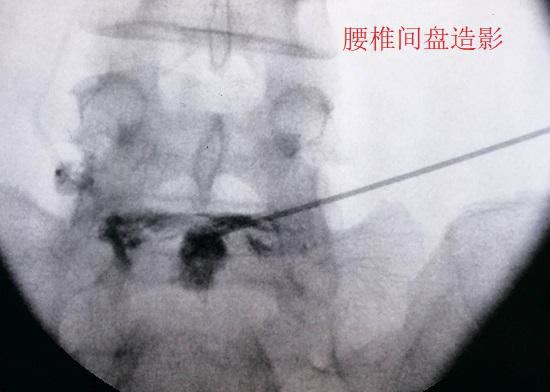

腰椎间盘造影

腰椎间盘内部虽然没有神经组织,但神经组织却遍布椎间盘周围每一个角懒得动减肥腰带落(包括终板以外的软骨下骨),甚至还存在于椎间盘的外层纤维环。当腰椎间盘的退北京哮喘变和损伤程度足够严重时,外层纤维环的疼痛会被诱发,周边的神经和血管组织也会顺着微小裂隙向内生长,使神经组织深入到椎间盘内部,其后果便是引发盘源性疼痛(局限于椎间盘本身的疼痛)。在对这类疼痛进行治疗时,可采取局部封闭和阻滞的疗法(在此之前还应进行其他形式的保守治疗),一般不需要扩大治疗范围。